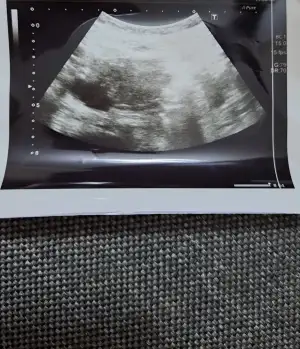

Kizlar bu ay klomen ile yumurta takibi yapildi. Pcos degilim ama yinede kullanmam gerekiyormus. Ilaca adetin 2.gunu basladim  cuma gunu bitti pazarteside kontrole gittim adetin 8.gunuydu. Üc yumurtan olusmus dedi. 12 14 mm dedi. Carsamba bida gel dedi. Bugun gittim 10.gunum bugun de 12 14 19 mm dedi 19 mm olan yumurta sagliksizmis aciklama yapmadi sagliksiz yumurta ne demek oluyor kistlesmemi var acaba  diger ikisi saglikli gorunuyor dedi. Benim anlamadigim iki gun oncede 12 14 mm den soz ediliyordu. Bugun yine 12 14 mm dedi cuma gunu tekrar gel dedi. Cok endiseliyim acaba o iki yumurtam gelismiyor olabilir mi? Iki gunun ultrason fotograflarini atacagim anlayip yardimci olabilecek biri varsa cok sevinirim mm olarak ben mi yanlis anladim acaba